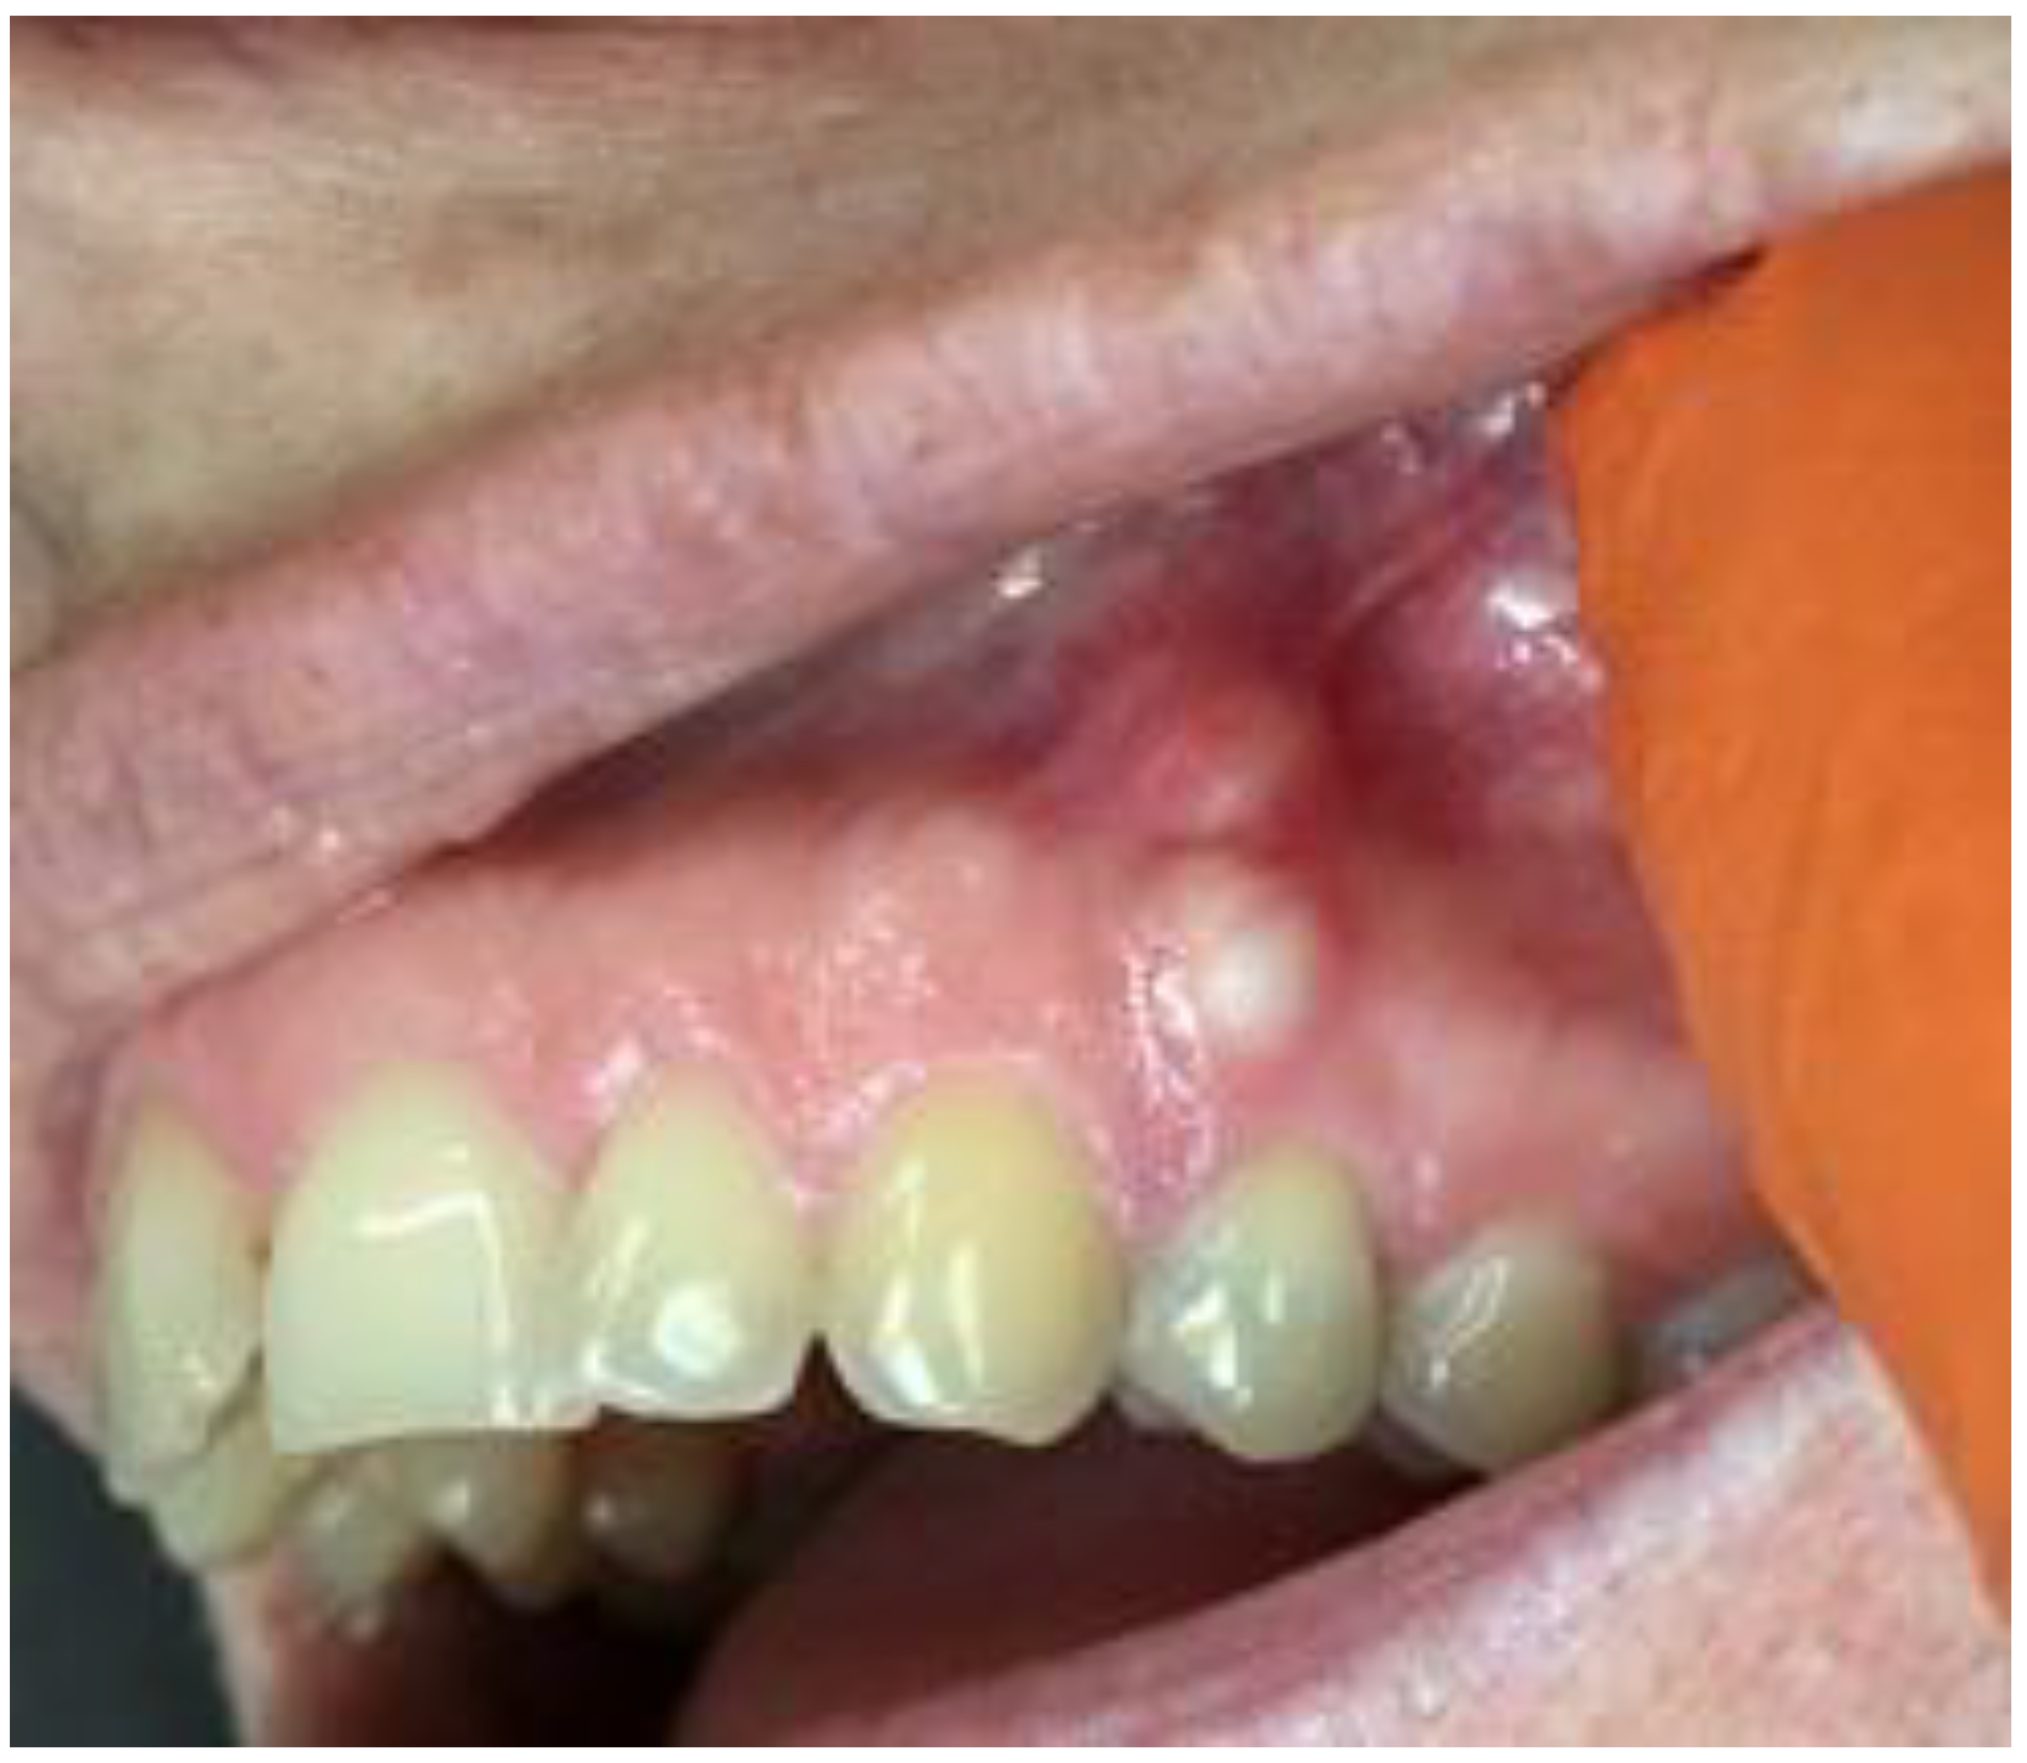

Figure 2. LPC expanding towards attached gingiva with buccal cortical plate resorption.

A 35-year-old female patient presented with a small, well-defined lesion on the attached gingival area, approximately 5/6 mm in diameter between roots of teeth 23–24, reported to the Privat Dental Clinic. The patient’s main concern was focused on gingival asymmetry and a tumor-like mass, painless and sometimes tender on tooth brushing. Clinical anamnesis revealed the occurrence of this asymptomatic mass for over 6 months. Because of swelling and atypical cortical expansion, the patient was referred for consultation and treatment. The patient was generally healthy without any chronic illness or important medical and dental past. A routine panoramic radiograph revealed a well-defined, radiolucent, left maxillary lesion located between the roots of the canine and first maxillary premolar (Figure 1 and Figure 2).

Clinically, teeth remain vital, non-displaced, stably situated in the alveolar socket with visible asymptomatic solitary swelling on the buccal gingiva with visible perforation of buccal cortical plate, not fluctuant on palpation. No ulceration or perforation through the attached gingiva was present. Presented cystic lesion was unilateral, painless in examination, and well related with adjacent expanded gingiva. Neither inflammation nor abscess formation was present. Both premolars responded well to cold stimulus. Surrounding teeth dental and periodontal status was good, all vital signs normal, and there was no periodontal disease without inflammated sockets or any other pathologies in surrounding bone and periodontal structures.